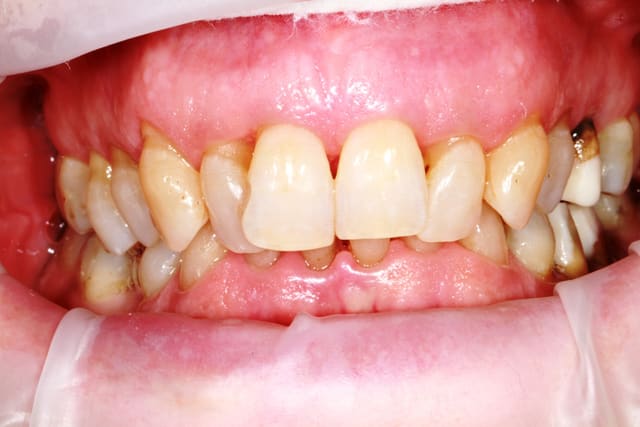

patiente 62 ans région Parisienne, appelle pour un avis, son praticien, paro, imlpanto etc... lui dit que sa paro n'a plus besoin de soin et propose pour les 6 antérieurs (j'ai le devis sous les yeux) 6 Inlay Core et 6 CCM...

Les panos sont du départ, les photos sont après un nettoyage ...profond et soins.